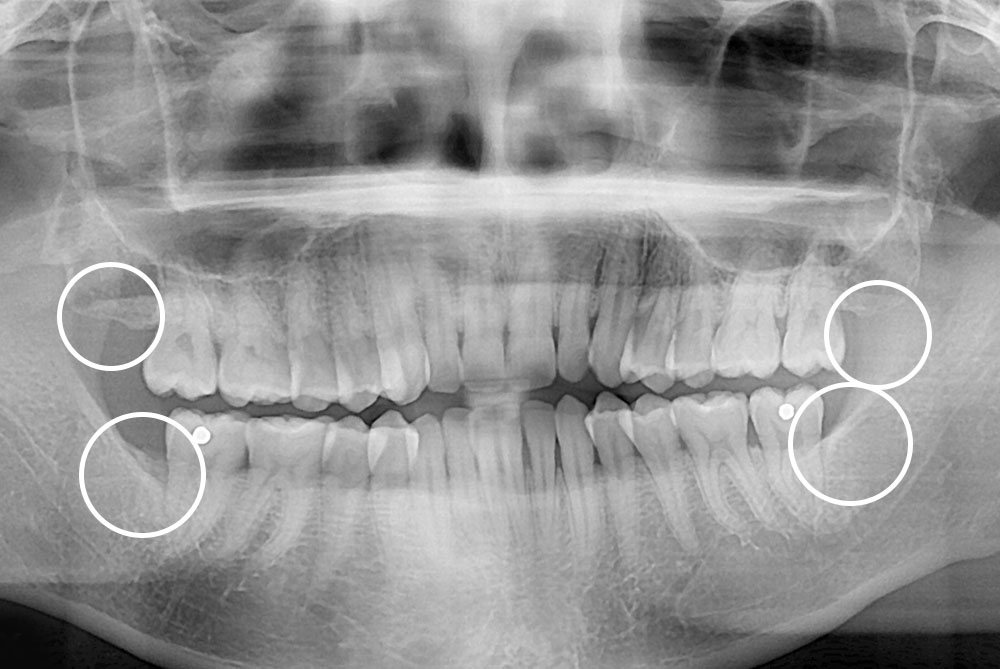

[사랑니] 매복 사랑니 발치

치료후 : 2019-11-09

세종치과는 구강악안면외과학 박사이신 원장님이 발치하는 치과입니다.